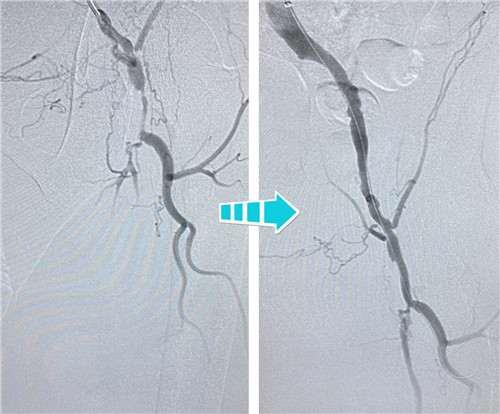

右側(cè)完全閉塞的髂血管順行開通無果,但這也難不倒我們經(jīng)驗豐富的鼓醫(yī)和石醫(yī)介入專家們,當(dāng)即決定由“順穿”改行“逆穿”。逆穿導(dǎo)絲難度大,技術(shù)要求高,十分考驗術(shù)者的操作手法和預(yù)判,專家團隊經(jīng)過內(nèi)膜下破膜逆行,一次性準(zhǔn)確對吻成功,同樣擴張球囊、植入支架,血流瞬間恢復(fù)暢通。